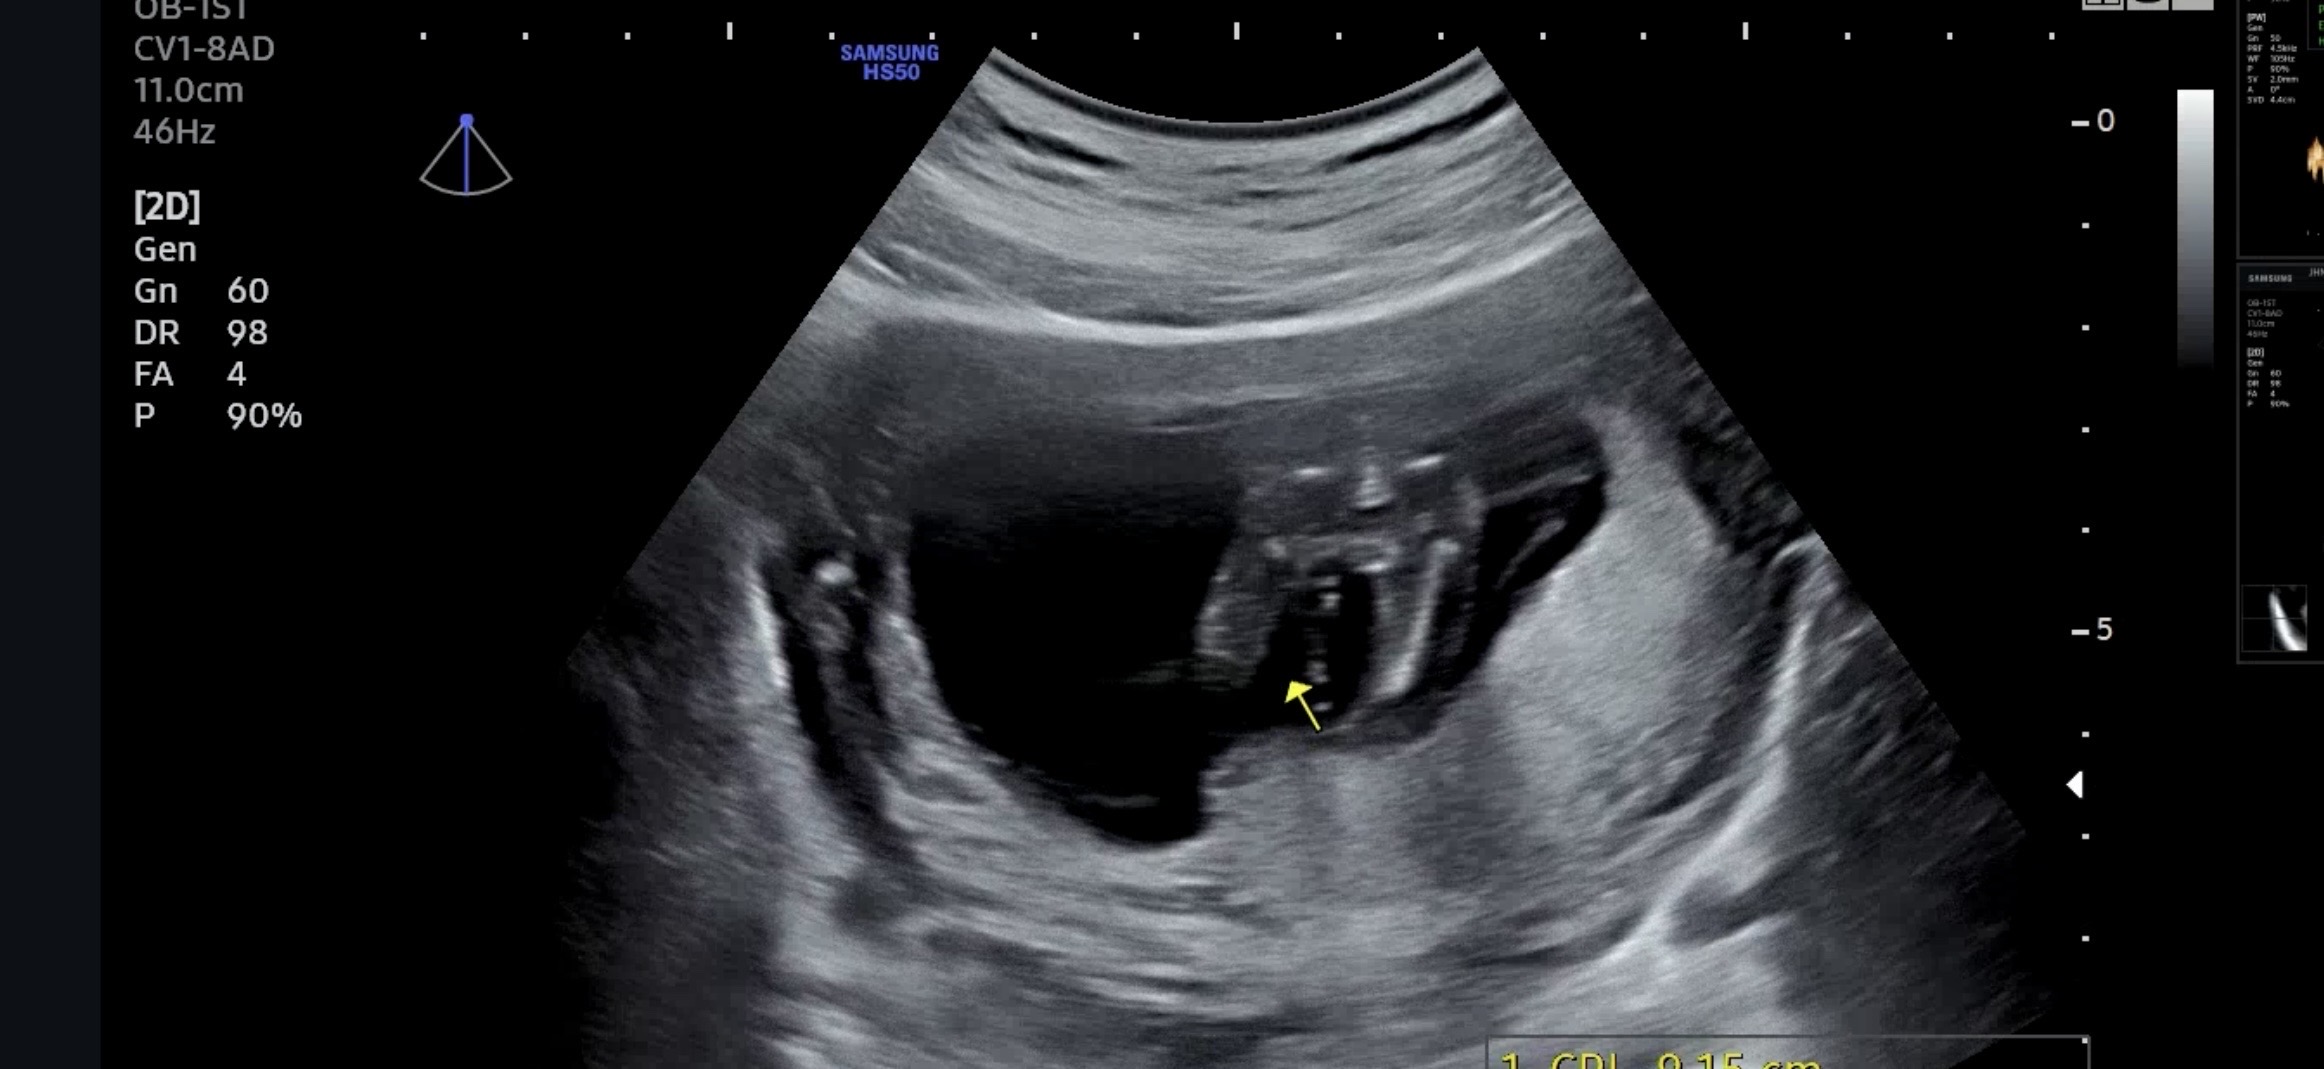

15주 초음파 성별!

오늘 서브병원에서 촘파확인했는데 선생님이 오늘은 딸인것같다는데 고추가 늦게 나오는 경우도 있어서 다음주되어야 정확히 알 수 있다는데 딸가진 마미들 어떤가요?